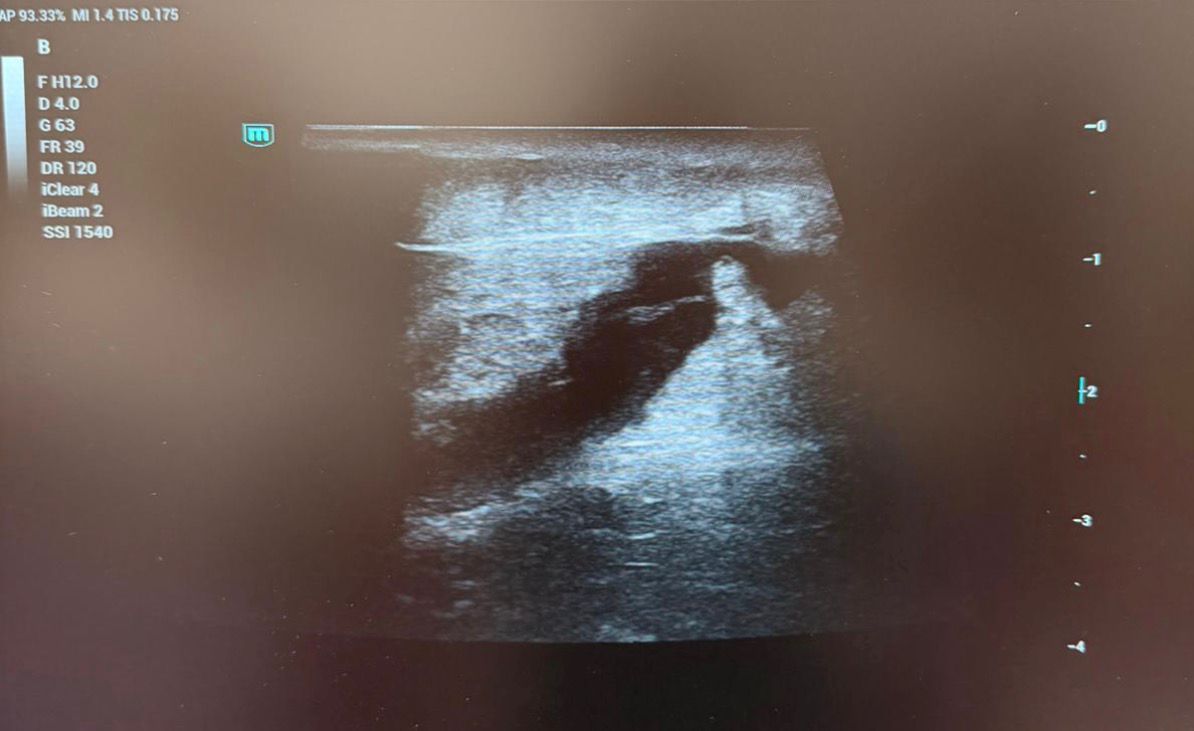

Ante la sospecha de una colección profunda postraumática, se realiza ecografía en la consulta para orientar el diagnóstico.

Hallazgos ecográficos

La ecografía identifica una colección hipoecoica homogénea, bien definida, situada entre la fascia del cuádriceps y el tejido celular subcutáneo, con despegamiento fascial nítido, hallazgo característico del síndrome de Morel-Lavallée.

No se observan signos de rotura fibrilar del cuádriceps ni flujo Doppler interno.

Dada la extensión de la colección y la clínica de tensión local, se decide realizar drenaje ecoguiado, obteniéndose contenido serohemático y logrando una reducción inmediata del volumen.